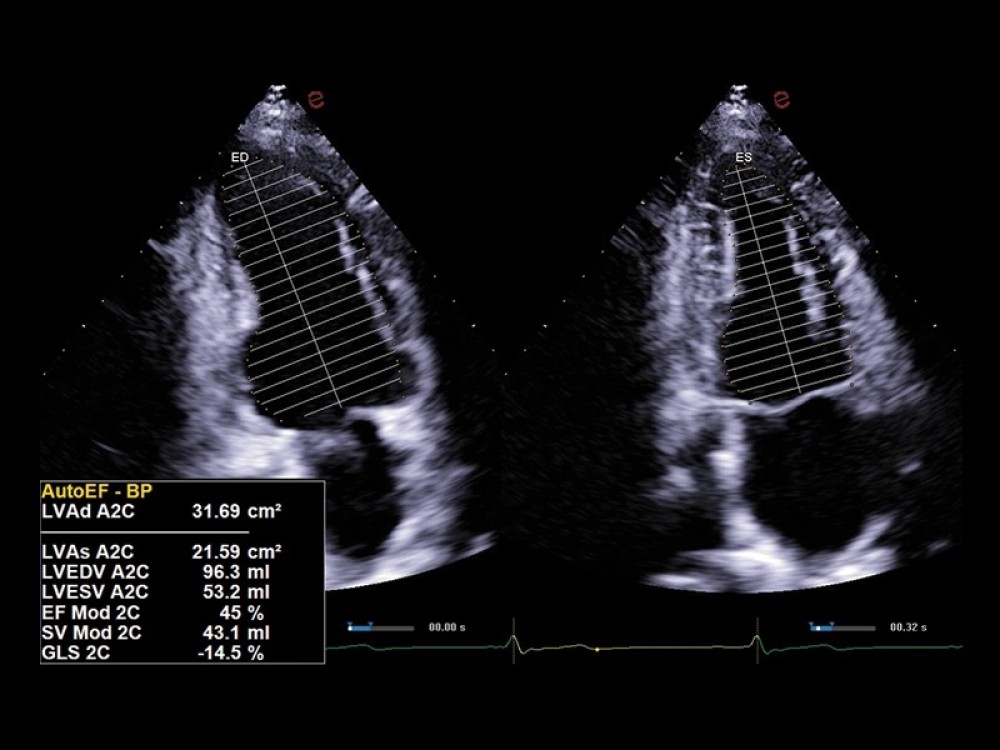

Kardiovaskulyar və Obstetrik AI Paketləri: Avtomatik ölçmələr və strain görüntüləmə vasitəsilə kardiovaskulyar və obstetrik müayinələrdə diaqnostik dəqiqlik artırılır.